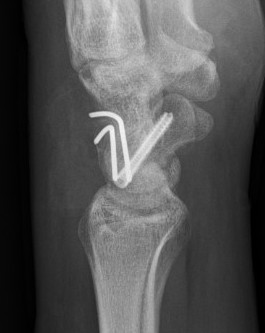

Lateral xray

Distal radius / lunate / capitate: not aligned, spilled teacup

Normal versus spilled tea cup appearance on lateral with spilled tea cup

Perilunate fracture-dislocations / Trans-scaphoid perilunate

- ORIF scaphoid fracture with headless compression screws

- assess stability of scapho-capitate and scapholunte joint (often ligaments intact and stable)